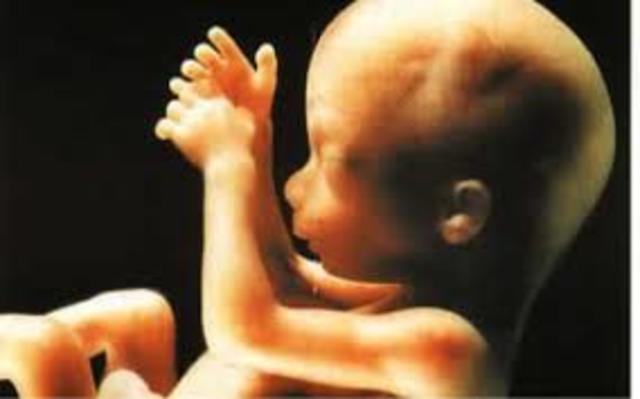

El ser que poco a poco va creciendo en tu interior ya deja de ser un embrión para convertirse en feto y se alimentará exclusivamente de la placenta a través del cordón umbilical. Por ello, es muy importante que comiences a tener una dieta sana y equilibrada porque será beneficioso para ti y el bebé.

Ya estamos en la semana once de embarazo, a punto de cumplir el primer trimestre. El cuerpo de tu bebé poco a poco se va alargando y su cabeza seguirá viéndose y siendo más grande que el resto de su cuerpo.

El niño mide unos 6 centímetros y su peso oscila entre los 8 y los 14 gramos. La mayor parte de las estructuras internas ya están formadas y, a partir de ahora, seguirán perfeccionándose y creciendo. El aparato genital externo del bebé empieza a definirse, aunque con los ultrasonidos de la ecografíaaún no es posible distinguir el sexo del feto. Con esta semana, termina el período de "embriogénesis", durante el cual el embrión está más expuesto a los peligros que podrían perjudicar la correcta fo

El feto mide unos 7 centímetros y pesa alrededor de 14 gramos.

A partir de esta semana, su peso y su longitud aumentarán mucho más rápidamente. Ya ha aprendido a respirar. El cartílago óseo empieza a convertirse en hueso y el cuerpo empieza a crecer más rápido que la cabeza.

Las orejas y los ojos se están moviendo hacia su posición. Ya han aparecido los 27 huesos de la mano y ya ha empezado a experimentar el sentido del tacto. Ya t